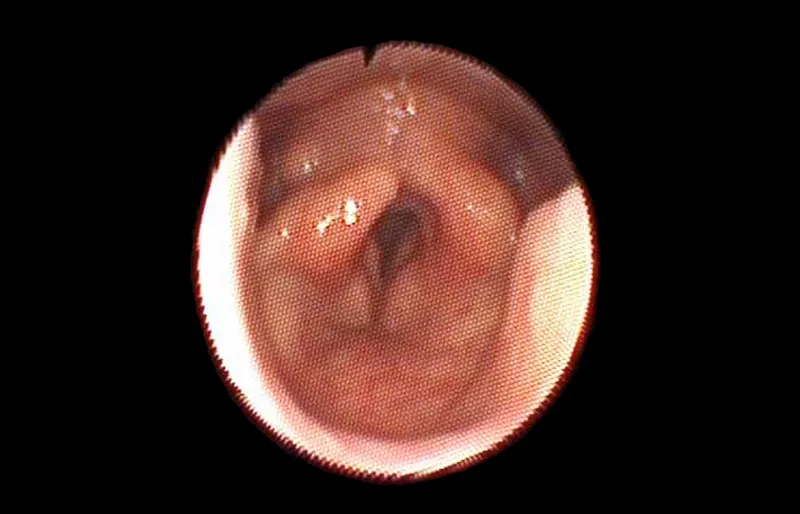

Endoskopija Beograd - endoskopski snimak glasnica

Predstavlja metodu izbora za pregled trećeg krajnika ili grkljana kod dece. Na ovaj način se može dokumentovati nalaz u spoljašnjem uvu ili stanje bubne opne. U nosu se endoskopskim putem vide nosni hodnici u koje se otvaraju sinusi, i može otkriti pražnjenje gnoja ili krvi iz sinusa, koje se standardnim pregledom ne može videti.

Na ovaj način se vrši detaljan pregled zadnjih partija nosa, nosnog sprata ždrela, otvora slušnih tuba, gornje površine mekog nepca, grkljana, donjeg sprata ždrela i vrši tzv. „screening“ traheobronhoskopija, odnosno pregled dušnika i dušnica.